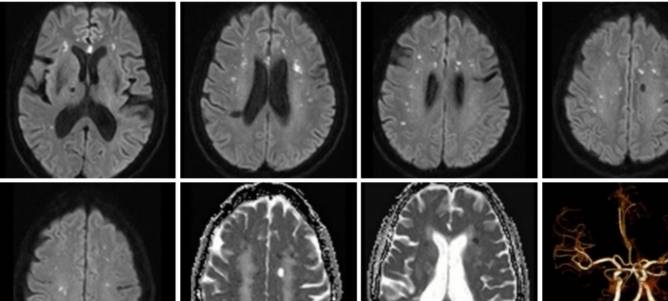

病例12

左侧肢体无力2天。

脑寄生虫病、低灌注脑梗死、基底动脉尖综合征丨3分钟读片 ...

病例13

女,35岁,体检发现头颅MR异常。